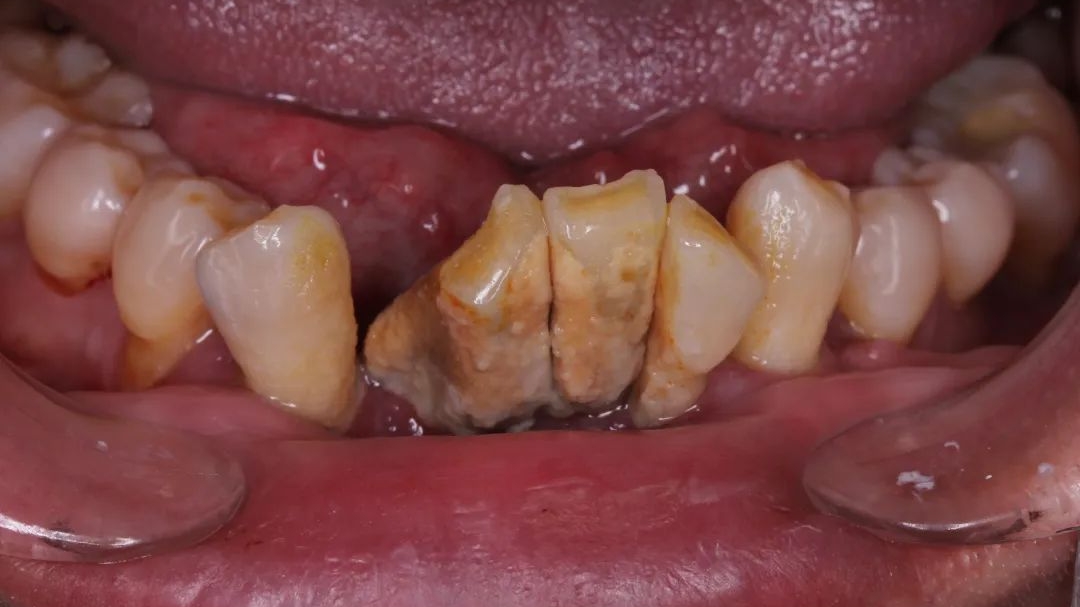

大量牙结石,导致牙齿松动移位,图源:作者提供

再再后来,牙齿不仅仅松动了,它们可能还开始移动位置了——牙齿和牙齿之间的缝隙越来越大。而之前松动的牙齿开始摇摇晃晃,有的还会出现牙齿的疼痛!

这时候再不看牙,光想着吃点药止一下痛,其实已经开始无济于事了。牙根开始暴露出来,牙齿的松动越来越严重。